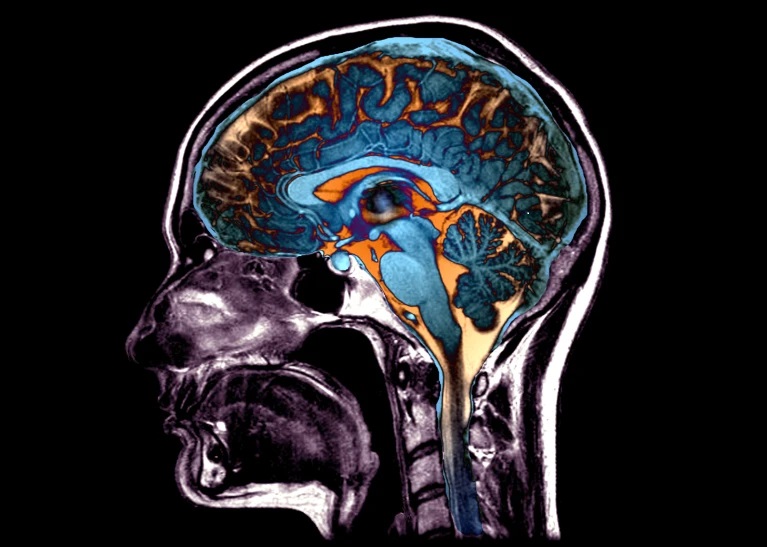

大脑的某些部分往往会与其他区域一起萎缩和变形。图片来源:Zephyr/SPL

衰老不仅会导致头发变白,随着时间的推移,大脑中的一些区域还会逐渐萎缩,发生微妙的解剖结构变化,这在磁共振成像(MRI)扫描中是可见的。论文作者之一、美国宾夕法尼亚大学的生物医学成像专家Christos Davatzikos说:“人眼无法感知与这种衰退相关的系统性大脑变化模式。”